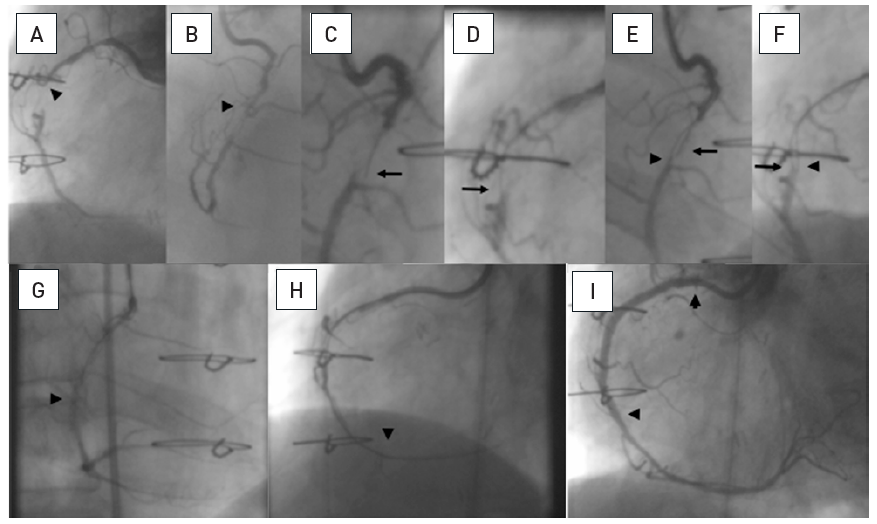

The fact that CTOs are specifically addressed as a subset of coronary lesion with additional rating is historically based on the fact of previously very low success rates of CTO PCI. There is no clinical evidence that would justify to consider a CTO a less severe lesion than a high-grade stenosis. The success rate of a proposed PCI for a CTO must therefore be taken into consideration as compared to alternative modes. A recent decision algorithm for indicating CTO PCI is based on the presence of symptoms and viability, which is basically the same reasoning that governs PCI indication in general [164164. Galassi AR, Brilakis ES, Boukhris M, Tomasello SD, Sianos G, Karmpaliotis D, Di Mario C, Strauss BH, Rinfret S, Yamane M, Katoh O, Werner GS and Reifart N. Appropriateness of percutaneous revascularization of coronary chronic total occlusions: an overview. Eur Heart J. 2016;37:2692-700. ] ( Figure 10).